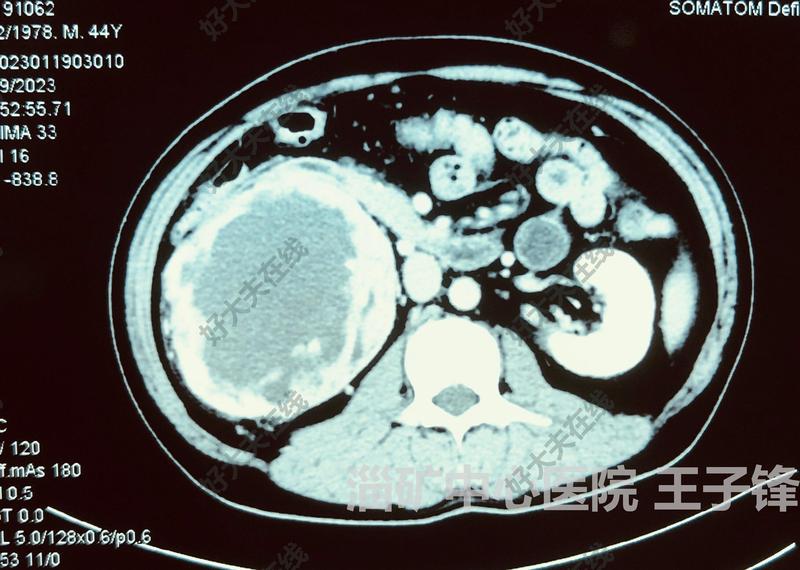

治療前 患者右腎腫瘤,直徑約13cm,侵及十二指腸,擬行后腹腔鏡腎癌根治備開(kāi)放手術(shù) 治療中 后腹腔鏡下完成腎癌根治,術(shù)中見(jiàn)腫瘤侵犯十二指腸,仔細(xì)游離,部分十二指腸漿肌層破裂,長(zhǎng)約5cm,予以修補(bǔ),手術(shù)順利 治療后 治療后7天 術(shù)后患者恢復(fù)好,術(shù)后1周出院